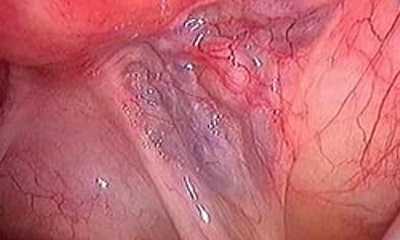

Варикоз на яичках у мужчин

Иное название заболевания варикоцеле. Варикоз на яичках у мужчин (фото 4) вызван повреждением вен, по которым идет отток крови от семенника и канатика. Если у мужчины наблюдается варикозное расширение вен нижних конечностей, то при тяжелой, либо сидячей работе, он имеет все шансы заиметь варикоз яичек.

У мужчин, как правило, заболеванию подвергается в основном левое яичко. Это связано с возможным пережимом вены сосудами кишечника. Варикозное расширение на яичках у мужчин наблюдается у 15% населения. Застой крови в области малого таза способен вызвать даже варикоз полового члена.